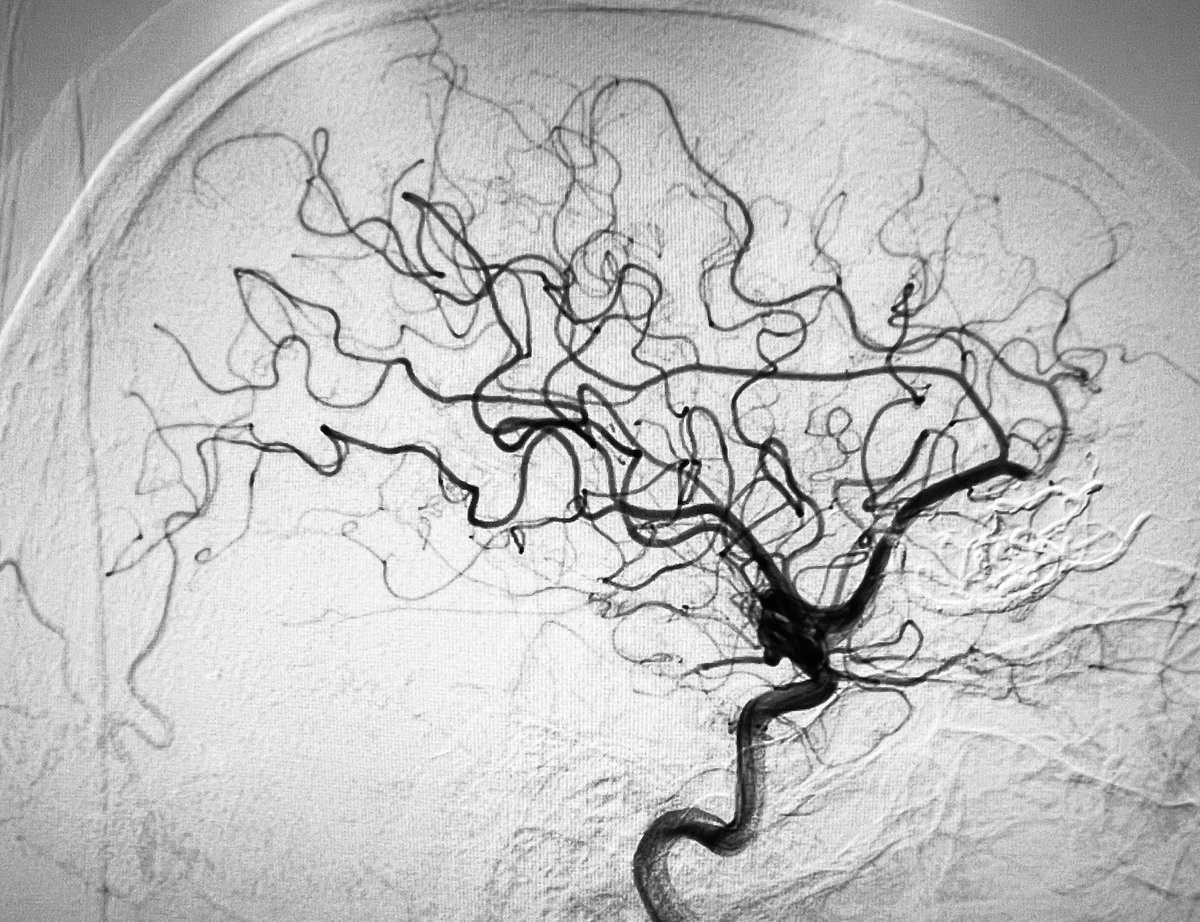

M1 acute occlusion/ICAD (good collaterals, ASPECTS 8): 90 minutes for DAPT loading dose. 60 minutes for solumbra>angioplasty >stenting to achieve mTICI 3 and a great recovery.